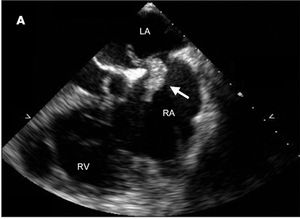

Chest pain and dyspnea of acute onset prompted a 49-year-old man to seek urgent medical attention. Two months earlier, he had sustained fractures to the right arm and both ankles after a 25-ft fall. Ten days before presentation, the patient’s rehabilitation physician had discontinued daily enoxaparin because of improved mobility and a presumed decreased risk of thromboembolism.